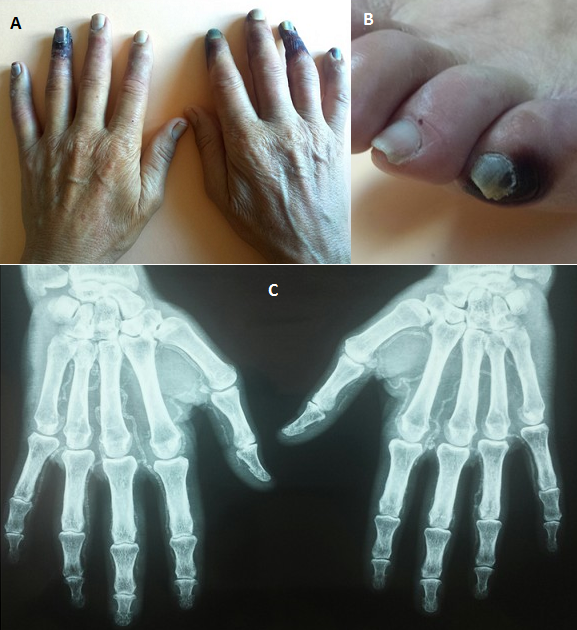

La nécrose digitale est une complication invalidante de diversespathologies. Un patient âgé de 60 ans,tabagique chronique et diabétique de type 2 depuis 8 ans compliqué de néphropathie diabétique en hémodialyse, présente depuis un mois des paresthésies et une froideur des mains suivies par l'apparition d'une bulle nécrotique à la pulpe des doigts évoluant rapidement vers la nécrose. L'examen clinique trouve une abolition des pouls radial, cubitalet pédieux ainsi qu'une gangrène sèche de 3 doigts et une ischémie froide des autres doigts sans sclérodactylie (A). L'examen du pied objective une nécrose du 5ème orteil gauche (B). Le doppler artériel montre une athérosclérose diffuse et une abolition du flux dans les artères interdigitales. La radiographie des mains montre des calcifications diffuses dessinant la cartographie artérielle anatomique de la main (C). Le diagnostic de nécrose digitale par athérosclérose calcifiée extensive était retenu. L'athérosclérose avec ses facteurs de risques habituels peut entraîner une artérite digitale du membre supérieur (résultant d'embolies distales à partir de la lésion d'athérosclérose), mais de façon plus exceptionnelle qu'au niveau des membres inférieurs. Les lésions d'ischémies sont aggravées par les calcifications artérielles favorisées par l'urémie chronique et les désordres du métabolisme phosphocalcique connus des patientshémodialysés. Le diagnostic différentiel est posé essentiellement avec les connectivites, les causes hématologiques et les causes toxiques. Le traitement est étiologique mais sutout symptomatique (antalgiques, vasodilatateurs, antibiotiques). L'amputationdoit être différée au maximum, sauf en cas de complication infectieuse, car des lésions qui paraissent irréversibles peuvent guérir par un traitement médical rigoureux.